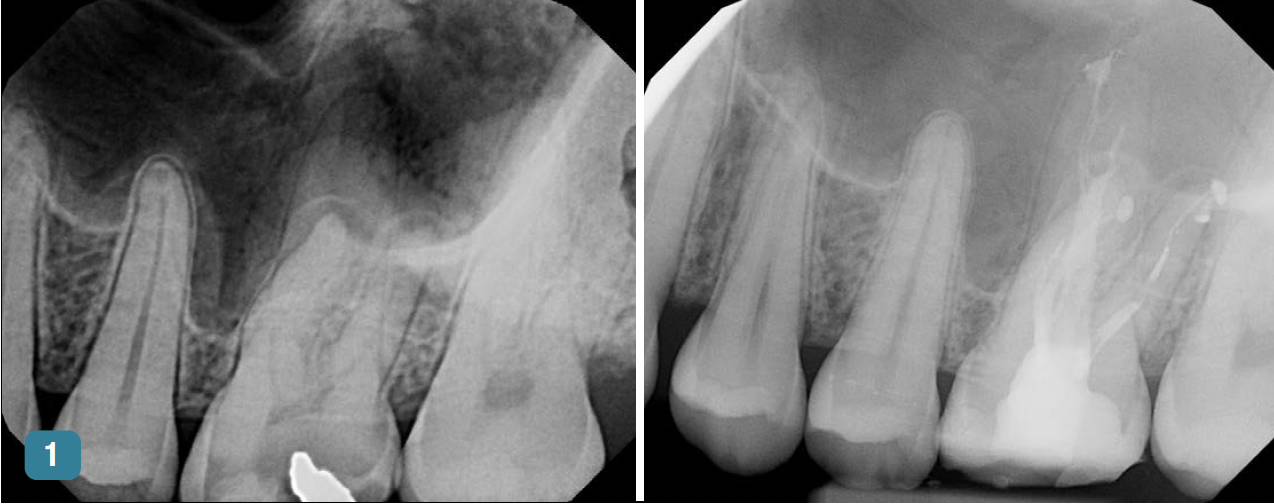

Figure 1 and Figure 2 provide examples of some cases that the author treated using the single-visit endo-restorative workflow. Despite the complex or challenging anatomy shown in these radiographs, the canals were able to be thoroughly irrigated by the multisonic irrigation system that was used with this workflow. For these cases, the one-day treatment workflow and the use of multisonic irrigation as described in this article enabled successful root canal treatment and improved patient satisfaction.

Fig 1 Using the endo-restorative workflow described in this article, the complex anatomy shown in these radiographs was able to be irrigated by multisonic

irrigation. Fig 1, left panel: Preoperative radiograph of tooth No. 14 with acute periapical abscess and dental caries in a 20-year-old male patient with good dental

and overall health. A filling had broken, and the patient had postponed treatment. Fig 1, right panel: Postoperative radiograph (after the single-visit endo-restorative

Figure 1